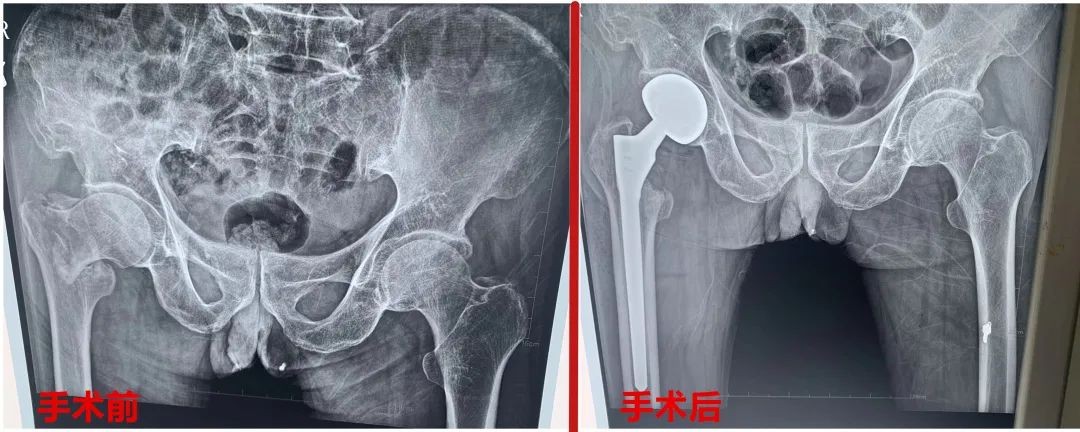

山东商报·速豹新闻网 张洪燕 通讯员 边晓欢为持续增进人民群众健康福祉,建设人民满意的医疗卫生服务体系,切实提高人民群众的健康水平。近日,菏泽鄄城